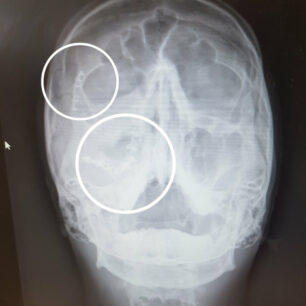

RTG s vyznačením titanu.